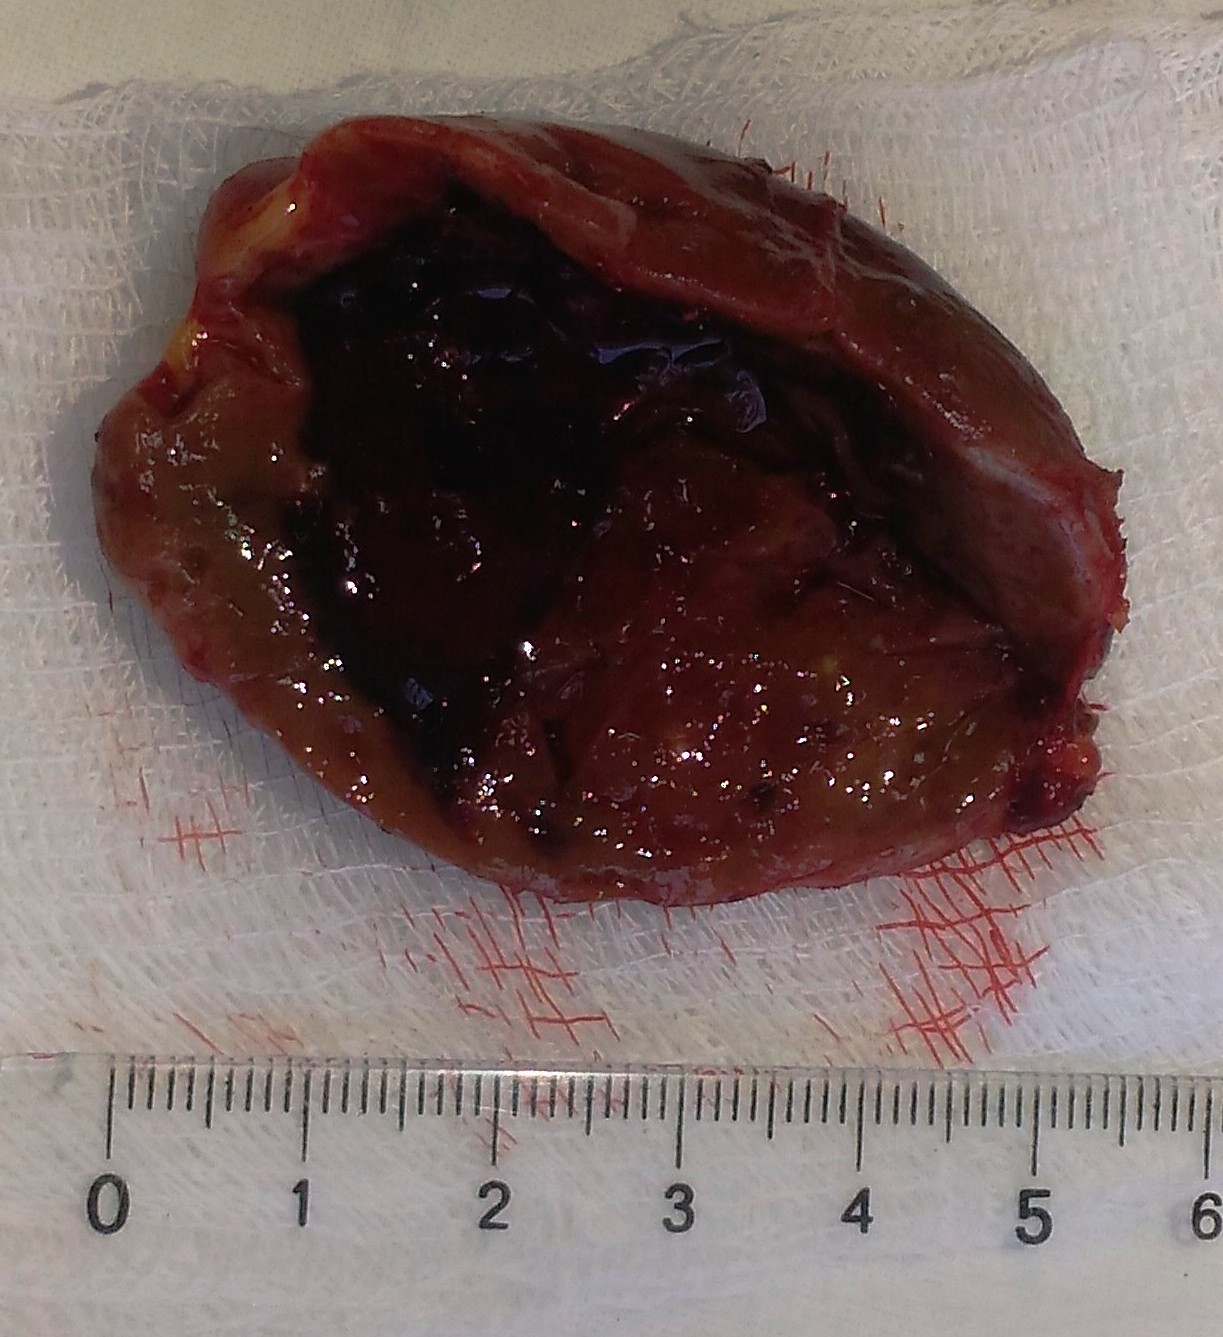

С клиническим диагнозом “первичный гиперпаратиреоз, смешанная форма; аденомы правой и левой нижних ОЩЖ” 28.02.2017 больной был взят на операцию. Во время интубации трахеи отмечалась ее деформация и смещение до 5 см от средней линии вправо. При ревизии в области средней трети левой доли ЩЖ определяется резко увеличенная аденома ОЩЖ размерами 6,0 × 3,5 × 2,5 см с кистой в нижнем полюсе до 1,5 см в диаметре. Аденома удалена. В области средней трети правой доли, симметрично по сравнению с аденомой слева, найдена еще одна аденома ОЩЖ 2,5 × 1,5 × 1,0 см с кистой до 1,5 см в диаметре. Аденома также удалена. Масса удаленной аденомы слева – 40 г, справа – 3,5 г. При патогистологическом исследовании: светлоклеточные аденомы ОЩЖ с кистозно расширенными железами (рис. 2).

Рис. 2. Аденомы околощитовидных желез: а – выделение гигантской аденомы ОЩЖ слева; б – определение размеров аденомы ОЩЖ слева после ее удаления; в – взвешивание гигантской аденомы ОЩЖ на электронных весах; г – взвешивание удаленных аденом ОЩЖ; д – схема топического расположения удаленных аденом ОЩЖ; е – макроскопический вид удаленных аденом ОЩЖ на разрезе.